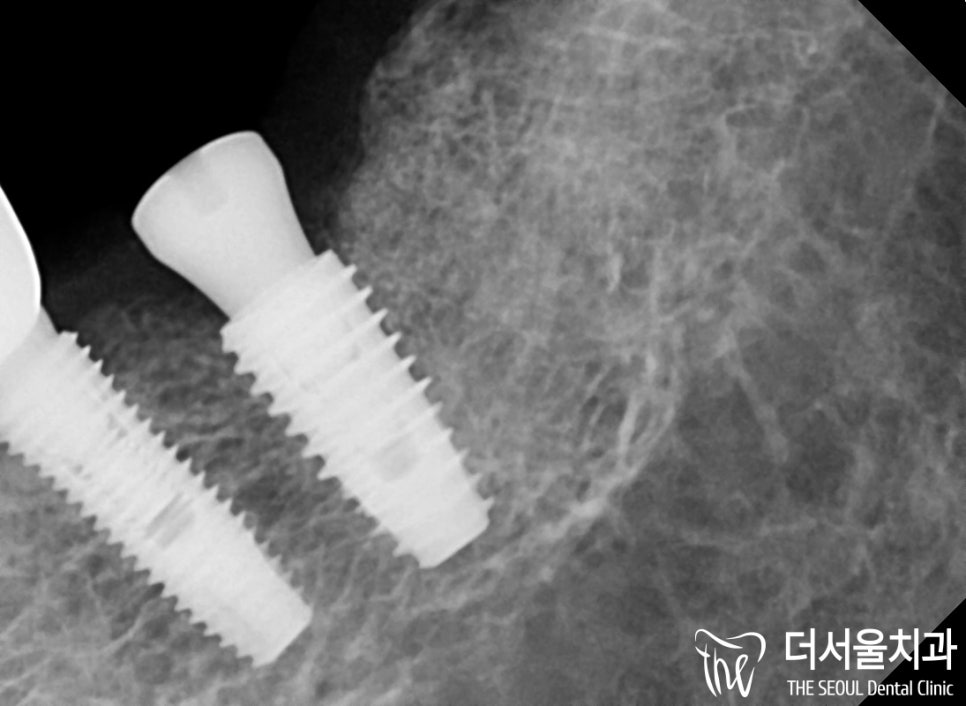

『좀 더 확대해서 살펴볼까요?』

정해진 위치에 계획했던 각도 그대로

단단하게 심어져 있는 것을 볼 수 있습니다.

옆에 있는 인접한 보철과

적당한 거리로 자리를 잡고 있는지,

추후 올라갈 최종 보철도

자연스레 제작이 될 수 있는 공간인지!

지금 당장이 아닌 미래에도 문제 없이

사용을 할 수 있는 것인지!

하나하나 살펴본 다음 신중하게 진행했습니다.